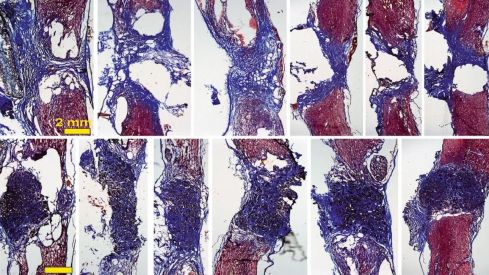

Los tejidos ‘colonizan’ el espacio hueco de la escisión en la médula espinal gracias a las espumas de grafeno creadas en el ICMM CSIC.

De esta manera, cuando se coloca el scaffold en la médula espinal –en este caso en un modelo de rata con la médula espinal completamente seccionada a nivel torácico–, "vemos que aparecen gran cantidad de vasos sanguíneos, que son fundamentales para nutrir el nuevo tejido, y neuritas (los filamentos que unen unas neuronas con otras)". La investigadora explica que con esto se observa “cómo las neuronas que han sobrevivido en la zona alrededor de la lesión proyectan sus prolongaciones a través del scaffold y lo invaden en toda su extensión 3D". Todo esto, además, mejora con el tiempo: los resultados son incipientes tras 10 días de implante, pero son mucho más prometedores a los 4 meses.

"Nuestros scaffolds de óxido de grafeno reducido favorecen el crecimiento de vasos sanguíneos más abundantes y más grandes, y neuritas más abundantes, más largas y, además, distribuidas de manera más homogénea en el espacio de la lesión", destaca Serrano.